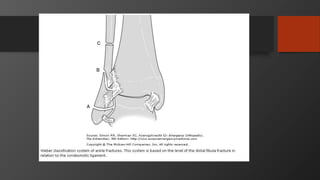

Ankle Fractures

Imaging

• AP, Lateral

• Mortise view

• CT scan

• Especially posterior malleolus